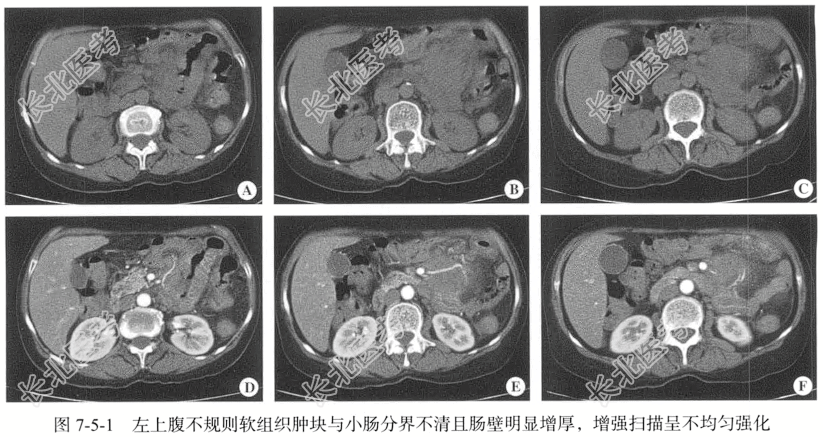

【影像图片】见图7-5-1。

【手术所见】小肠Treitz韧带起始处小肠系膜见大小约为6.00cm×7.00cm肿瘤,肿瘤固定导致空肠起始处肠管受压狭窄。

【病理诊断】ALK阴性的间变性大细胞肠系膜淋巴瘤。